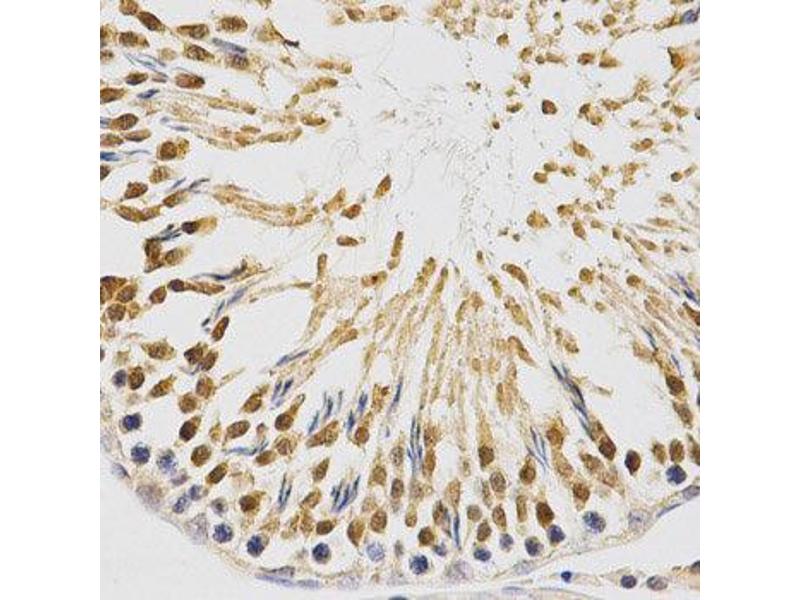

L'immunohistochimie (IHC) désigne le processus de détection des antigènes dans les cellules d'une coupe de tissu en exploitant le principe de liaison spécifique des anticorps aux antigènes des tissus biologiques. Elle est largement utilisée dans le diagnostic des cellules anormales comme celles que l'on trouve dans les tumeurs cancéreuses et dans la recherche fondamentale pour comprendre la distribution et la localisation des biomarqueurs et des protéines exprimées de manière différentielle dans différentes parties d'un tissu biologique. Visualiser une interaction anticorps-antigène peut être accompli de plusieurs façons. Dans le cas le plus courant, un anticorps est conjugué à une enzyme, comme la peroxydase, qui peut catalyser une réaction produisant une couleur, ou marqué à un fluorophore.